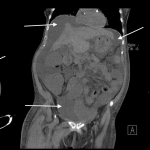

ABDOMINAL/PELVIC CT-SCAN WITH ONLY IV CONTRAST

Key features of ascites seen in this imaging modality are:

- Density similar to water (transudative ascites): typically between -10 and + 10 HU

- Density slightly above water (exudative ascites): can be above 15 HU

- Does not enhance with IV contrast: typically this should not occur, however delayed enhancement of ascites can occur in some cases. Perfused organs should appear significantly brighter then surrounding ascites.

The gallery below organizes examples of how ascites will appear on a abdominal/pelvic CT-scan with the usage of only IV contrast. Click on the thumbnails below to open up the gallery: